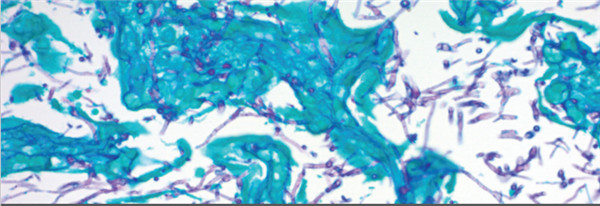

3.Cat#KAA-1 GMS Stain Kit

組份:硝酸銀溶液,甲胺硼砂溶液,氯化金溶液,淺綠色溶液,龍膽紫溶液,碘溶液,革蘭氏脫色劑,亞硫酸氫鈉溶液,氧化液,硫代硫酸鈉5%,紅色復(fù)染,酒石酸溶液

目的:改良的Gomori甲基六胺-硝酸銀染色劑(GMS染色試劑盒)旨在用于真菌,基底膜和某些機(jī)會(huì)性生物(如卡氏肺孢子蟲)的組織學(xué)可視化。 此外,該程序還將顯示放線菌和相關(guān)物種,諾卡氏小行星諾卡氏菌和某些包囊細(xì)菌。 鉻酸和危害較小的替代氧化劑均可使用。

結(jié)果圖: